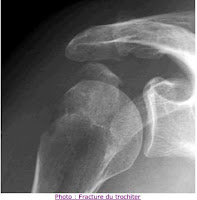

2-  fracture isolée du trochiter (fréquentes en ski)

Elles se présentent sous différents types anatomiques

- les unes sont des fractures de tout le massif

- les autres des fractures partielles, operculaires.

et de 2 manières différentes:

a/ de manière subaigue sous la forme d' une épaule impotente immédiate après chute directe sur le moignon de l'épaule, avec abduction contrariée; craquement; douleurs vives; impotence fonctionnelle totale; ecchymose retardée du bras à 48 heures et dissociation activo-passive des amplitudes d'épaule comme dans le tableau de rupture de coiffe, la seule différence résidant dans l'anamnèse avec la notion de chute sur le moignon de l'épaule. Le diagnostic est radiologique par les 3 radiographies de face qui déroulent le trochiter; mais ne pas hésiter à recourir au Scanner si besoin. Le traitement est fonction du déplacement